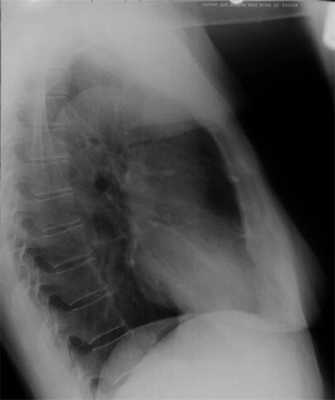

В левой боковой проекции передний контур сердечно-сосудистой тени представлен двумя дугами. Верхняя выпуклая дуга образована восходящей аортой, которая переходит в дугу и нисходящую аорту. Нижняя дуга обусловлена правым желудочком, верхняя часть которого представлена легочным конусом. Правый желудочек прилегает к грудине на протяжении 5-6 см. На границе легочного конуса и восходящей аорты образуется угол открытый кпереди. Между грудиной и передним контуром сердечно-сосудистой тени прослеживается треугольной формы участок, образованный проекцией легких.

По заднему контуру сердечно-сосудистой тени сверху вниз прослеживается аорта, легочной ствол и частично сосуды корней легких. Нижняя дуга образована левым предсердием и левым желудочком. Левый желудочек прилегает к диафрагме на протяжении 5-6 см, как и правый желудочек к грудине.

В левой боковой проекции прослеживаются все отделы аорты. Величина ретрокардиального пространства 2-4 см. Пищевод прилегает к левому предсердию и имеет вертикальное направление.

В левой боковой проекции не увеличенный левый желудочек не касается своим контуром контрастированного пищевода, нижняя полая вена четко дифференцируется в заднем кардио-диафрагмальном углу. В норме размер левого желудочка (ЛЖ), прилегающего к диафрагме, равен линейному размеру правого желудочка (ПЖ), прилегающего к грудной клетке - «желудочковый коэффициент», т.е. отношение указанных размеров ЛЖ/ПЖ=1. Увеличение левого желудочка в левой боковой проекции классифицируют по трем степеням изменений: